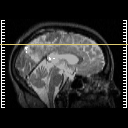

SPECT TL Study #8 -- Slice #39

[Home][Help][Clinical][Tour 1][Tour 2][Tour 3] Slice 39